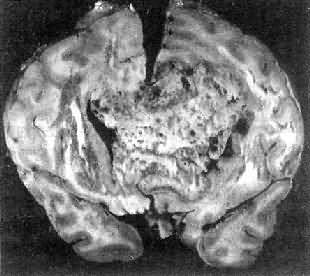

高度恶性的星形胶质细胞称为多形性胶质母细胞(glioblastoma multiforme),多见于成人。肿好发于额叶、颞叶白质,浸润范围广,常可穿过胼胝体到对侧,呈蝴蝶状生长(图16-24)。体因常有出血坏死而呈红褐色。镜下,细胞密集,异型性明显,可见怪异的单核或多核巨细胞。出血坏死明显,是其区别于间变性星形胶质细胞的特征。毛细血管明显增生,内皮细胞增生、肿大,可导致管腔闭塞和血栓形成。肿发展迅速,预后极差,患者多在2年内死亡。

图16-24 多形性胶质母细胞

在两半球内肿呈蝴蝶状,边界不清,切面见有出血、坏死及液化